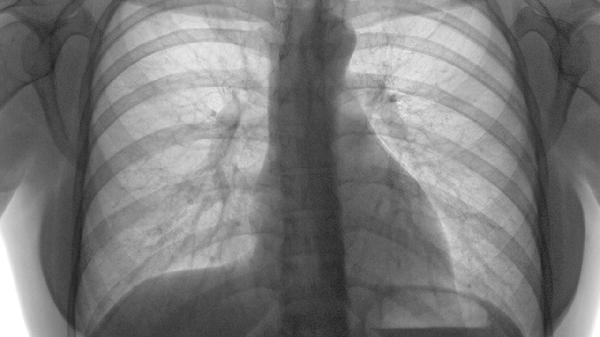

肋骨骨折患者除药物镇痛外,需保持患侧制动,避免剧烈咳嗽或深呼吸加重损伤。恢复期可适量补充富含钙质和维生素D的食物如牛奶、鱼类,促进骨骼愈合。疼痛持续不缓解或出现呼吸困难、发热等症状时,应立即复诊排除并发症。所有药物均须在医生指导下使用,不可自行调整剂量或联合用药。